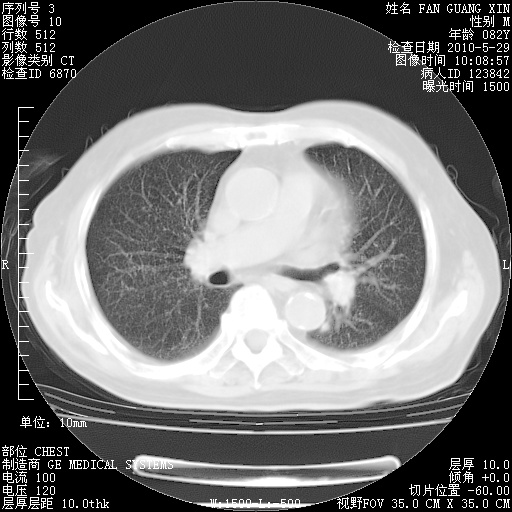

还需要哪些辅助检查?我们医院排除真菌感染没有任何检验方法,胸片好像能够排除肺部真菌感染。